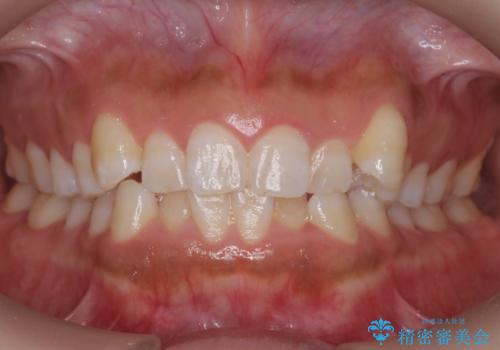

![[ 受け口傾向のマウスピース矯正 ] マイクロインプラントで行う確実な後方移動の症例 治療前](https://seimitsushinbi.jp/wp/wp-content/uploads/2024/04/5f0bc38a5dfbfee2c682d1aed8343d4d-500x350.jpg?v=1712301054)

![[ 受け口傾向のマウスピース矯正 ] マイクロインプラントで行う確実な後方移動の症例 治療後](https://seimitsushinbi.jp/wp/wp-content/uploads/2024/04/2095617952f97867f275f6769d72e82a-500x350.jpg?v=1712301056)

[ 受け口傾向のマウスピース矯正 ] マイクロインプラントで行う確実な後方移動